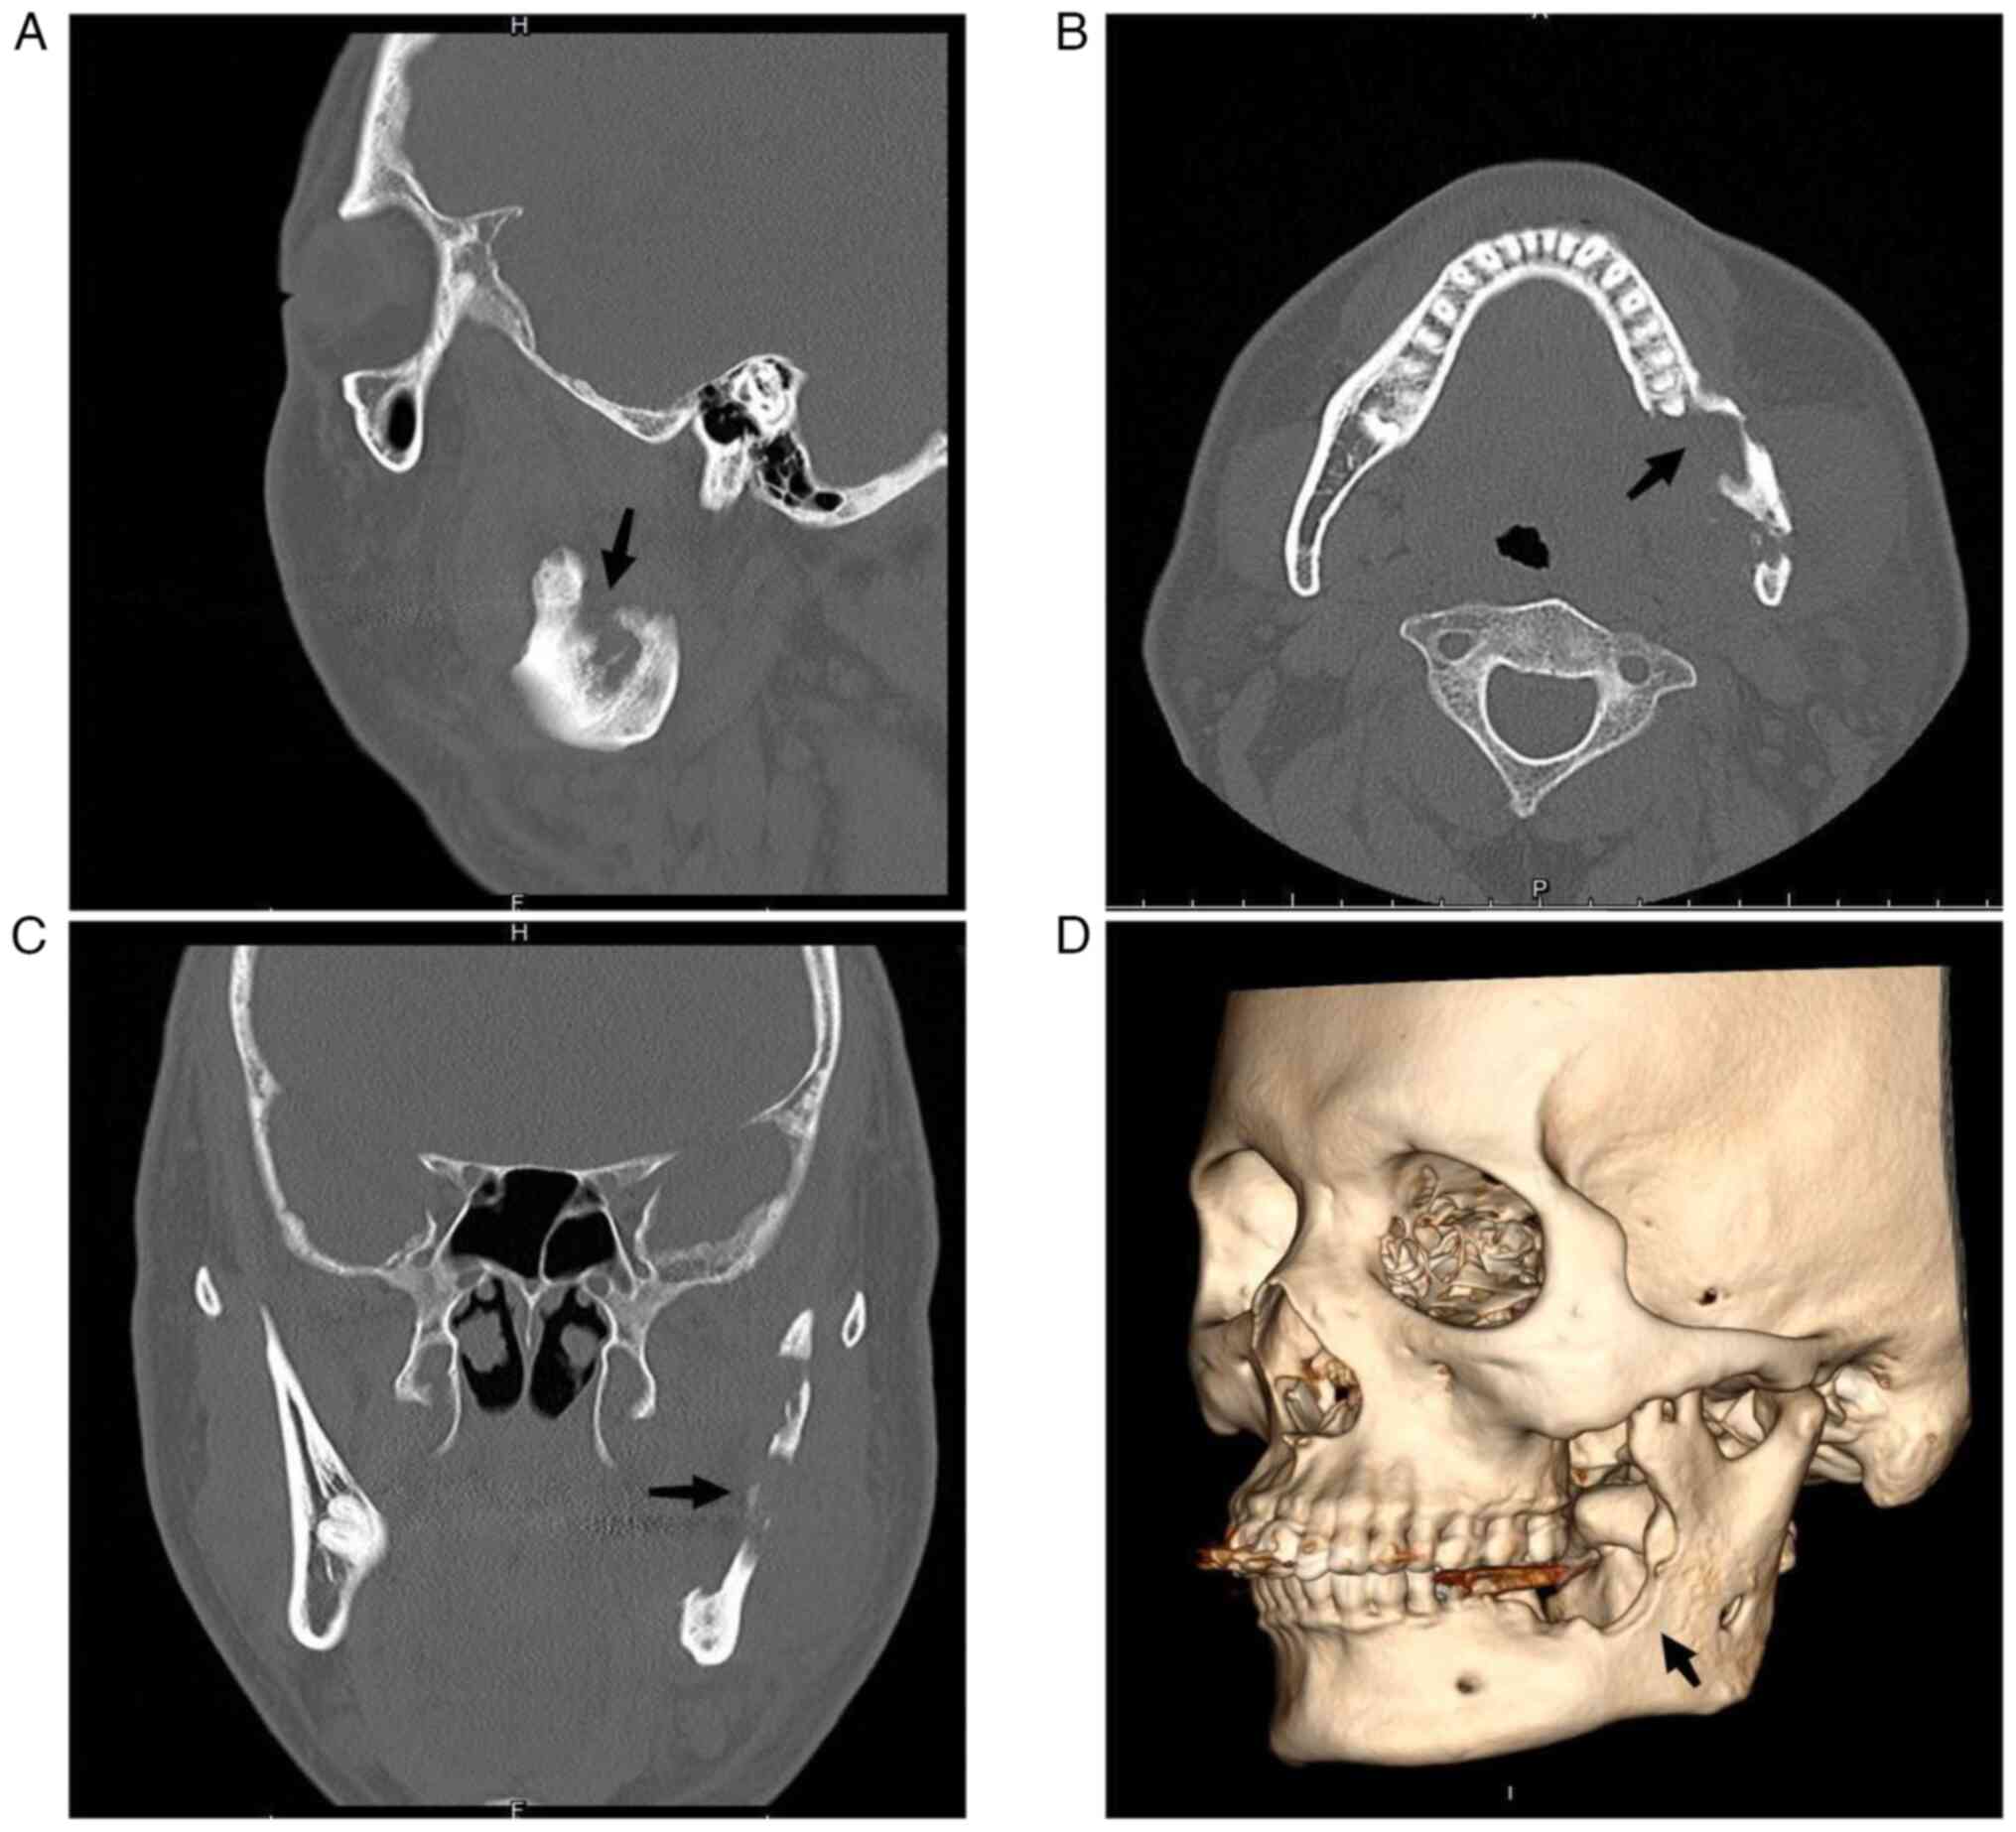

Figure 2

Mandibular CT scan prior to admission. (A) Sagittal view. Mandibular CT scan showed involvement of the left mandibular coronal process and ascending mandibular rami (black arrow). (B) Cross-sectional visual field. Mandibular CT scan revealed a local lamellar periosteal reaction with an increase in bone mineral density in unaffected areas (black arrow). (C) Coronal visual field. Mandibular CT scan showed significant destruction of the left ascending branch of the jaw with a soft tissue mass (black arrow). (D) 3D surface reconstruction (left maxillary surface) highlights the deformation of the left mandibular coronal process, rami and body (black arrow).

Radiographic assessments were based on reports from two or three independent radiologists. Panoramic radiographs revealed that the lower left third molar was missing, with resorption of the alveolar socket extending to the root apex area of the lower left second molar. In addition, a 0.5x1-cm low-density shadow with an indistinct boundary was discernible in the middle and lower portion of the left mandibular ascending branch (Fig. 1). At the sagittal plane (Fig. 2A), mandibular CT scan showed involvement of the left mandibular coronal process and ascending mandibular rami. Cross-sectional perimetry (Fig. 2B) revealed a local lamellar periosteal reaction with an increase in bone mineral density in unaffected areas. The coronal visual field (Fig. 2C) showed significant destruction of the left ascending branch of the jaw with a soft tissue mass. A 3D surface reconstruction (left maxillary surface, Fig. 2D) highlights the deformation of the left mandibular coronal process, rami, and body. Given these findings, concerns were raised regarding the possibility of an invasive or malignant bone tumor. After admission, a preoperative tissue biopsy was performed on the left mandibular lesion. The collected tissue, obtained from the affected site, underwent histopathological examination with Hematoxylin and Eosin (HE) staining. The diagnosis of squamous cell papilloma was conclusively confirmed based on the distinctive features observed in the stained biopsy specimens. Consequently, it was determined that complete resection represented the optimal course of action for the patient. The surgical procedure was performed by an oral and maxillofacial surgeon. A grayish-yellow mass measuring 3.0x2.0x1.5 cm was identified in the left masseter attachment area during the operation, which exhibited a texture akin to the tip of the nose, tough with medium consistency, and had unclear boundaries. In total, ~0.5 cm of the tissue surrounding the tumor was excised. No destruction was observed on the buccal side of the left mandible. The bone surface appeared waxy and rough, involving blurred boundaries. Numerous grayish-white papillary growths (white arrow) were visible along the left ascending mandibular branch (Fig. 3A). A resection involving the left mandibular body, the left ascending branch of the mandible and the coronal process was performed to address this diseased bone. Finally, a bone plate harvested from the medial iliac ridge of the left side was utilized to fill the bone defect within the left mandible. To ensure adequate fixation, the defect was secured using titanium plates and titanium nails. In the assessment of this mass, the primary goal was to differentiate between benign papilloma and squamous cell carcinoma, necessitating a meticulous analysis of cellular characteristics. The focus was in identifying any indicators of cell atypia, heightened mitotic activity and aggressive traits suggestive of malignancy. Furthermore, the presence of a distinct papillary structure supports the exclusion of squamous cell carcinoma. Clinical relevance, imaging studies and the expertise of two independent pathologists further bolster our ability to rule out malignancies from the list of potential diagnoses.